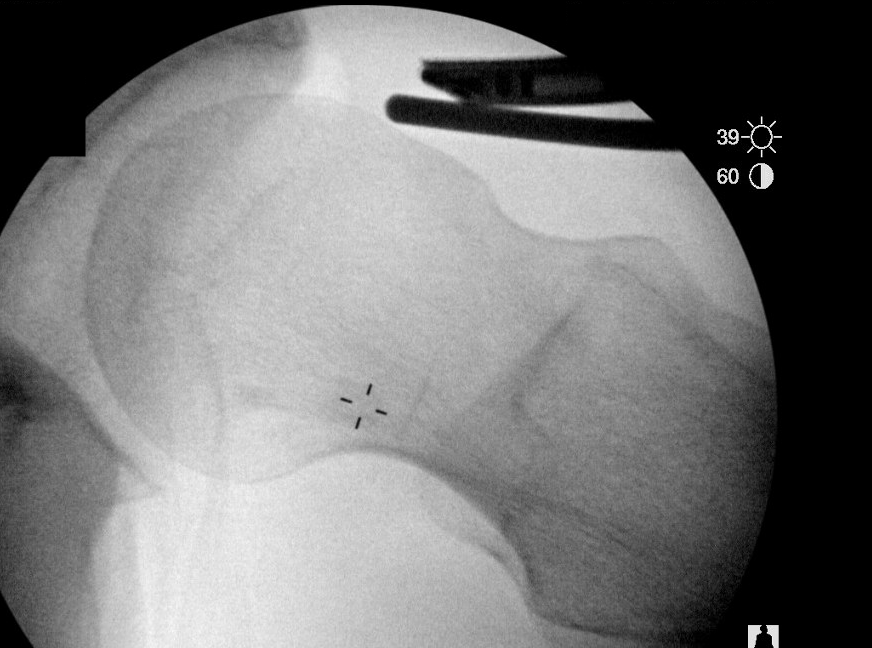

CAM resection

Anterior Cam

- hip flexed to 45 degrees

- image intensifer rotated 20 degrees posterior and 20 degrees distal to allow Dunn view

Anterior cam resection with hip flexed

Intra-operative Cam resection using Dunn view

Lateral Cam

- hip in extension / internal rotation

Lateral cam resection with hip in extension